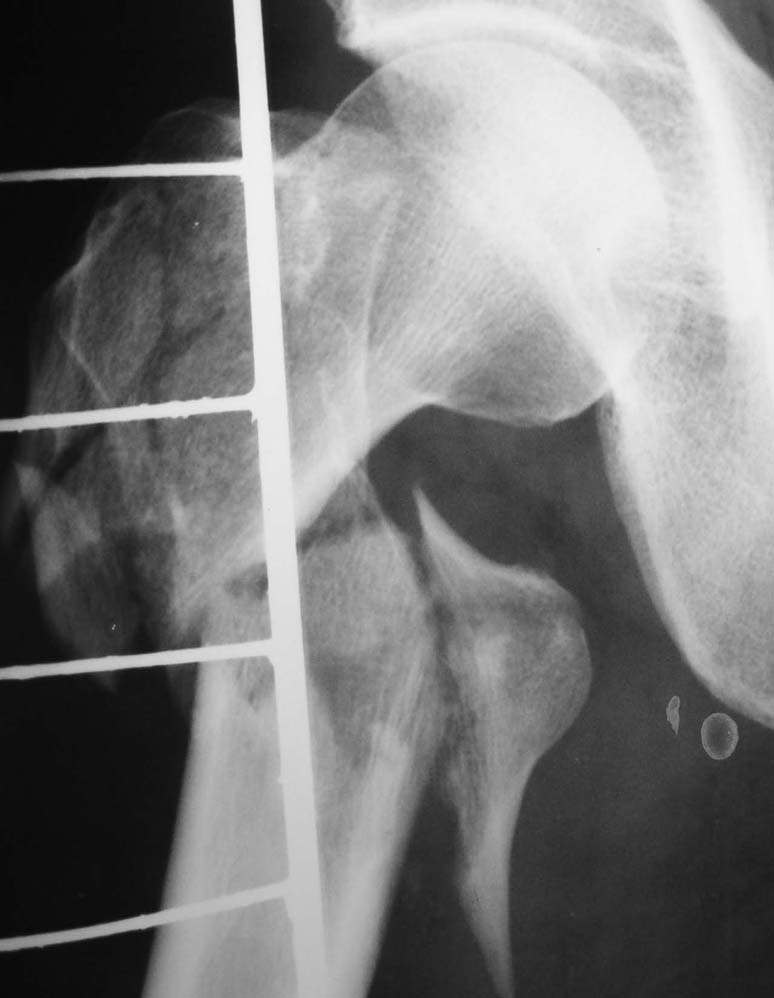

Другое наблюдение: Мужчина, 1957 г.р. Травма в результате ДТП 12.09.04г.

Диагноз: Закрытый оскольчатый подвертельный перелом правой бедренной кости со смещением отломков, оскольчатый перелом большого вертела, отрывной перелом малого вертела. Сопутствующие заболевания: Язвенная болезнь желудка, ремиссия.